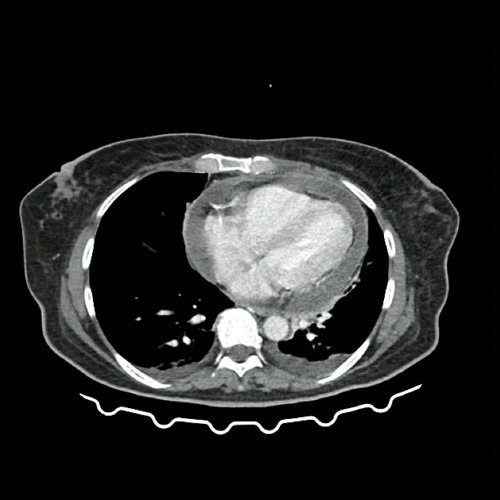

Anexo 1: TAC de tórax con contraste, corte axial. DÍA 0 06/09/2025

Asociado presentó como hallazgo derrame pericárdico severo (23 mm circunferencial) sin evidencia de compromiso hemodinámico ni signos de taponamiento con conducta expectante.

En dicha unidad se realizó tomografía con hallazgo de lesiones hipodensas en ambos riñones (descritas como probable origen inflamatorio-infeccioso), líquido libre periuterino con reticulación de grasa locorregional. Por hallazgo de hematometra se solicita interconsulta a Servicio de Ginecología, quienes descartan conducta quirúrgica de urgencia.